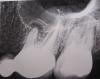

Альберта77 Опубликовано 22 марта, 2011 Автор Поделиться Опубликовано 22 марта, 2011 Выкладываю снимки (было и после лечения). Надеюсь, картина прояснится... Ссылка на комментарий

Dr.Ka Опубликовано 22 марта, 2011 Поделиться Опубликовано 22 марта, 2011 На снимках я красным выделила, в чем собственно проблема. На одном из корней - киста. Воспалительный процесс, который и привел к появлению кисты, обострился, поэтому появилось то, что Вы называете "флюсом" и боли. Совершенно верно то, что были пролечены каналы. Прошли ли боли после пломбировки каналов? Если нет, то каналы нужно перелечивать. Если да, то боли могут быть из-за выведения большого количества пломбировочного материала в полость кисты. Тогда только одно - ждать и наблюдать. А для разреза оснований в данный момент действительно нет.http://s55.radikal.ru/i150/1103/c1/ea47e0454e68.jpghttp://i039.radikal.ru/1103/ce/e0fb00350aa0.jpg Ссылка на комментарий

Альберта77 Опубликовано 22 марта, 2011 Автор Поделиться Опубликовано 22 марта, 2011 Спасибо за ответ. Но на втором снимке не киста. Это врач пасту лечебную закладывала и направила на рентген, чтобы убедиться, до конца прошла в канале. Зуб меня сейчас абсолютно не беспокоит. Только нарыв на десне. Ссылка на комментарий

Dr.Ka Опубликовано 22 марта, 2011 Поделиться Опубликовано 22 марта, 2011 Киста за неделю никуда не делась. Хорошо если она через месяцев 10-12 исчезнет. Так что на втором снимке - киста, заполненная пастой. Если микрофлора, вызвавшая появление кисты, убита при лечении канала, "нарыв" пройдет и всё наладится. Если нет, антибиотики помогут вряд ли. Ссылка на комментарий